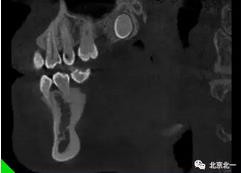

圖四:冠狀面截圖牙根位于唇側(cè),牙冠位于腭側(cè)。

圖五:矢狀位截圖可見(jiàn)牙冠截面。